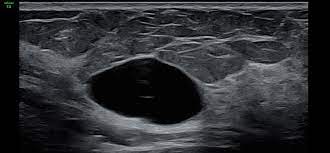

Die Mammasonographie ist eine Ultraschalluntersuchung der weiblichen Brust. Sie ist eine wichtige Ergänzung zur Tastuntersuchung und zur Mammografie. Der Brustultraschall kann die Mammographie aber nicht ersetzen. Mit dem Brustultraschall lassen sich die Gewebestrukturen der Brust gut untersuchen, vor allem bei sehr gewebedichten Brüsten junger Frauen. In der Mammographie sind manche Veränderungen bei sehr dichtem Gewebe oft schwer zu erkennen. Mit der Mammasonographie lassen sich besonders gut Zysten (mit Flüssigkeit gefüllte Hohlräume im Gewebe) von echten Tumoren unterscheiden. Mit dem Brustultraschall können ausser der Brust auch die Lymphknoten der Achselhöhlen untersucht werden. Der Brustultraschall ist völlig schmerzlos und mit keiner Strahlenbelastung verbunden, somit kann die Untersuchung auch bei Schwangeren problemlos durchgeführt werden und für Verlaufskontrollen beliebig oft wiederholt werden.

Die Untersuchung erfolgt in entspannter Rückenlage. Kontaktgel wird auf die Haut aufgetragen und der Schallkopf des Ultraschallgerätes aufgesetzt. Der Untersucher bewegt den Schallkopf so hin und her, dass er das gewünschte Ultraschallbild auf dem Monitor sieht und die jeweiligen Strukturen beurteilen und messen kann. Zusätzlich können Bilder für die Befundung gespeichert werden. Es werden systematisch beide Brüste nacheinander untersucht.